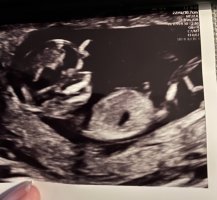

Her er ikke nub synlig dessverre13+4

Noen som snudde seg med ryggen opp, presset sammen som en liten ball inmerst i et "hjørne", så fort "kameraet" var på, så dette er dessverre det beste (og eneste) bildet.

Det er veldig tidlig for å se kjønn, men det ser ut som en jente nå, men det kan endre seg. Det er veldig små marginer for å måle mer eller mindre så du er nok 12+1, noen vokser litt mer og andre vokser litt mindre også, ofte er gutter litt større enn jenter også. Jeg tror kanskje nuben vil reise seg litt på denne og at det er en gutt, men enn så lenge ser det ut som jenteNoen som kan se noe kjønn på disse bildene?

Regnet ut i fra IVF egginnsett 12+1, men jordmor mente 12+4 etter å ha målt fosteret da disse bildene ble tatt